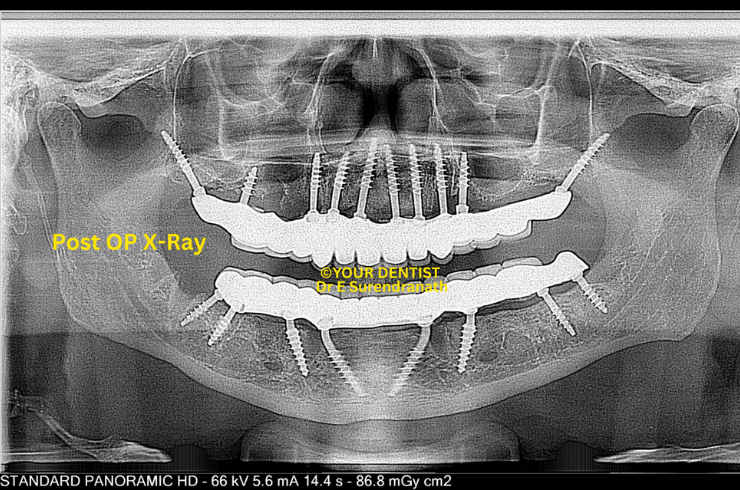

Basal & Cortical Implant - Post OP X ray